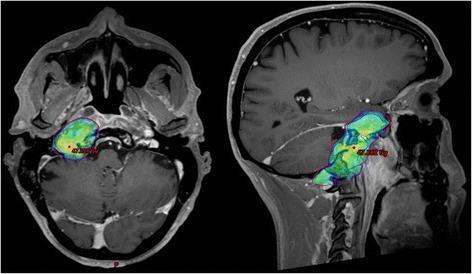

Patient was first diagnosed with locoregionally advanced, non-keratinizing nasopharyngeal carcinoma in 2010. After achieving complete remission following induction chemotherapy and concurrent curative chemoradiation, the patient subsequently developed distant and locoregionally recurrent disease. He received various treatments (neck dissection, radiotherapy to a bony metastasis, palliative chemotherapy, stereotactic re-irradiation of local recurrence) before initiation of anti- PD-1 immunotherapy with pembrolizumab in January of 2016. Following marked local progression 6 months thereafter, we performed re-re-irradiation of the recurrent tumor after careful evaluation and treatment planning. While treatment was well tolerated, the patient subsequently developed marked clinical and radiological signs of immunostimulation with mucosal irritation and swelling of lacrimal and salivary glands as described in the report. Immunotherapy with pembrolizumab was reinitiated, with re- staging showing excellent response with regression of all tumorous lesions. At the time of this report, following near complete recovery of inflammatory symptoms, the patient remains in excellent condition and free from recurrence under treatment with pembrolizumab.

患者于 2010 年首次诊断为局部晚期、非角化性鼻咽癌。在诱导化疗和同期根治性放化疗后达到完全缓解后,患者随后出现远处和局部复发疾病。在 2016 年 1 月开始接受抗 PD-1 免疫疗法帕博利珠单抗治疗之前,他接受了各种治疗(颈部清扫术、骨转移放疗、姑息性化疗、局部复发立体定向再放疗)。6 个月后局部进展明显,我们在仔细评估和治疗计划后对复发性肿瘤进行了再放疗。虽然治疗耐受性良好,但随后患者出现明显的免疫刺激临床和影像学迹象,如报告所述的黏膜刺激和泪腺及唾液腺肿胀。重新开始使用帕博利珠单抗免疫治疗,重新分期显示所有肿瘤病变均有极好的反应,完全消退。在本报告时,在炎症症状几乎完全恢复后,患者在帕博利珠单抗治疗下状况良好,无复发。